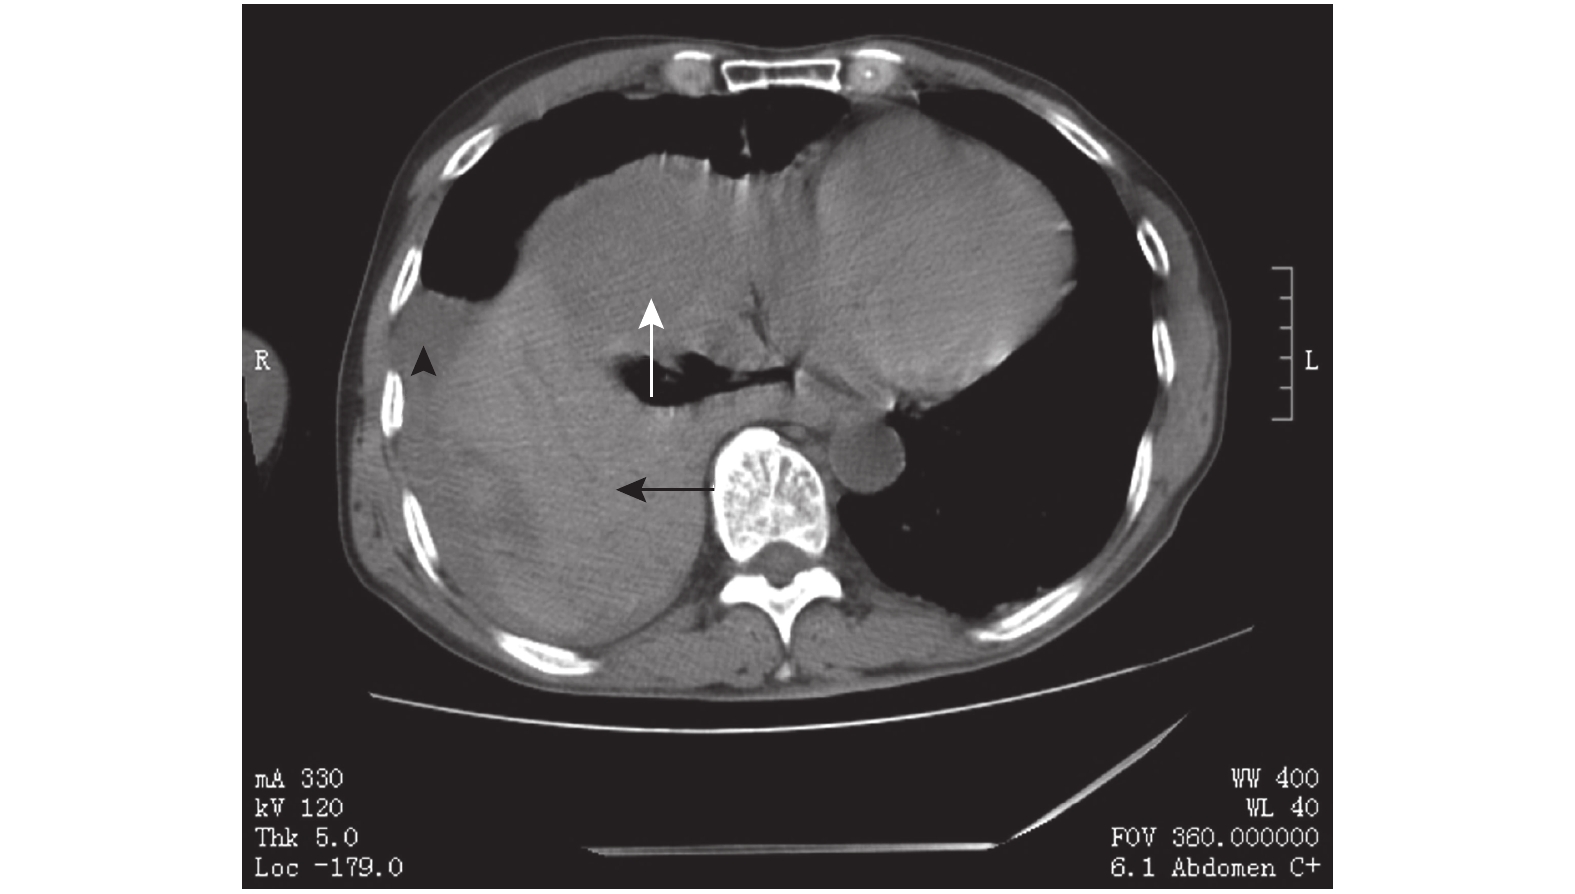

示肝癌(白箭)、肝臟(黑箭)、胸腔積血(黑箭頭)